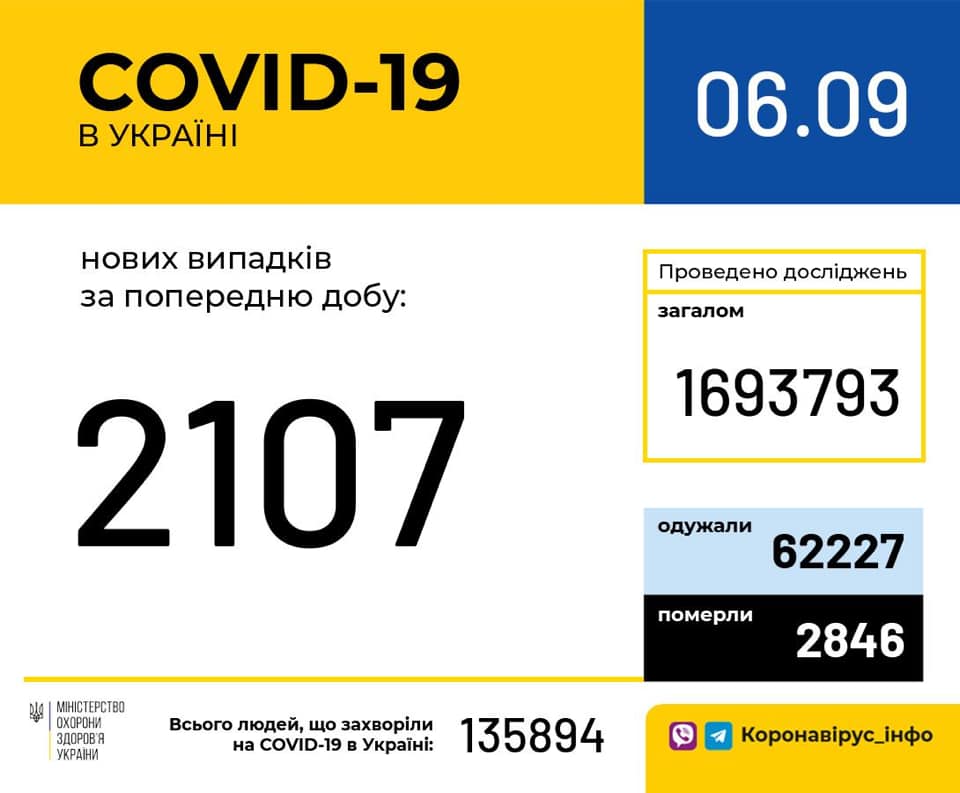

Більше 3 тисяч випадків захворювання на коронавірус зафіксували в Україні за добу

11.09.2020 09:37